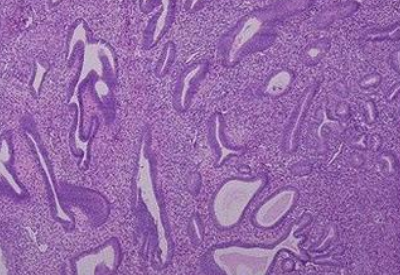

全自動白帶香蕉成人A片视频子揭示,宮內膜厚的原因可能是由於太多雌激素刺激子宮壁所致。子宮內膜厚的病症假如卵巢激素混亂,易導致異常子宮內膜厚,即子宮壁升值症,它是由於大量雌激素刺激子宮壁所致。臨床症狀為不規則的多量的異常子宮出血,病人可以在長期停經後出現持續的流血,醫學上可能疑為小產,也可體現為周期減少、經期延長,出血時間可達1個月。

白帶香蕉成人A片视频提醒若女性的下丘腦、垂體或是卵巢軸的某個階段失衡,或遭受多囊卵巢綜合征等病症的影響,都可能會使子宮壁較長期地持續性受雌激素作用,造成不排卵。這樣的話,子宮壁較長久的持續性受雌激素作用,無雌激素抵抗,缺乏規律性分泌期的轉換,會長期處於增生的情況,導致子宮內膜增生異常。

一般情況下,正常厚度為一至十mm,但白帶香蕉成人A片视频廠家提示它會跟隨激素水平的改變而出現繁殖和脫落的狀況,所以它的薄厚隨階段不同而相應改變。一般來說,子宮壁在月經完成後開始增長,在月經前1天達到最高值,然後功能層和組織血液一起流出,這個過程就是月經來潮。來潮環節中,隨著階段的差異,薄厚也各不相同。

子宮內膜厚能夠出現於任何年齡階段的女性群體之中,青春期、生殖期、圍絕經期或閉經後期均可發生。而如果是40歲以上的女性有這種情況,香蕉网视频在线观看就需要警惕病變的可能。子宮內膜增厚,也會造成女性在生殖期不排卵功血,所以除了病人朋友陰道出血以外,不孕症其實也是關鍵的病症。